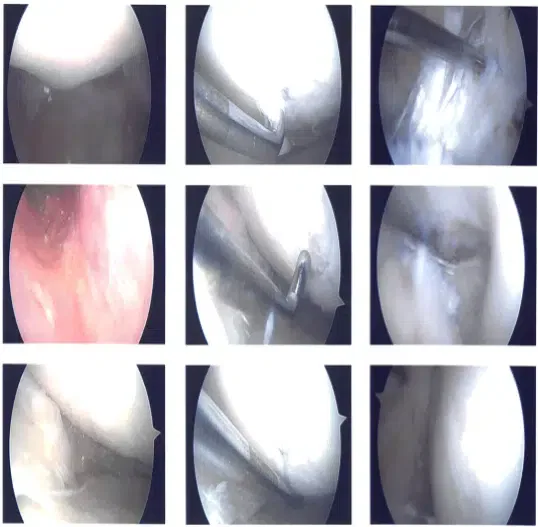

Lateral entry portal was used following an incision. Arthroscope was entered. Patellofemoral compartment and medial and lateral gutters showed normal anatomy. Pictures were taken.

Examination of the medial tibiofemoral compartment showed grade 3 to grade 4 osteochondral damage of the medial femoral condyle as well as degeneration of the medial meniscus and tearing.

There was grade 1 to grade 2 osteochondral damage of the medial tibial plateau also. There were no loose bodies out of the meniscus. Examination of the intercondylar notch showed degenerated and ruptured ACL.

Examination of the left tibiofemoral compartment showed lateral grade 3 to grade 4 osteochondral damage of the left femoral condyle and tear of the posterior horn of the lateral meniscus and undersurface of the meniscus.

Intraoperative images